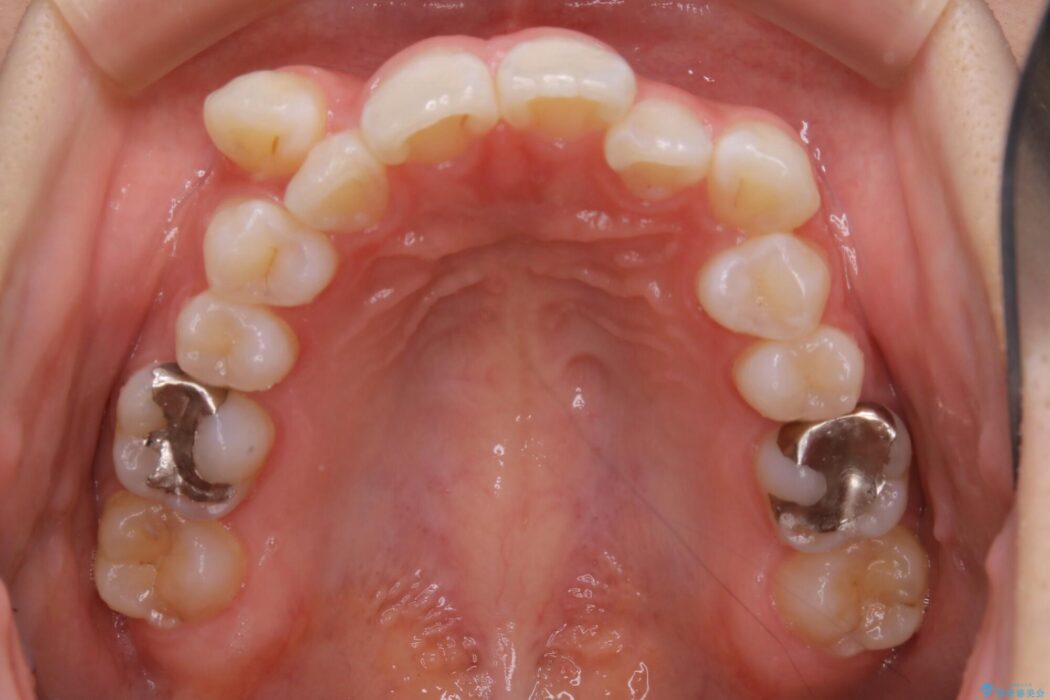

診査したところ叢生だけでなく生まれつき永久歯の欠損、いわゆる先天欠如により歯の本数が少ないため噛み合わせなどにも影響が出ている状態でした。

特殊な状況からの矯正治療となるため、抜歯する本数や位置、歯列を整えるにあたって必要なスペースの確保を慎重に計画し、インビザライン コンプリヘンシブパッケージでのマウスピース矯正を行いました。